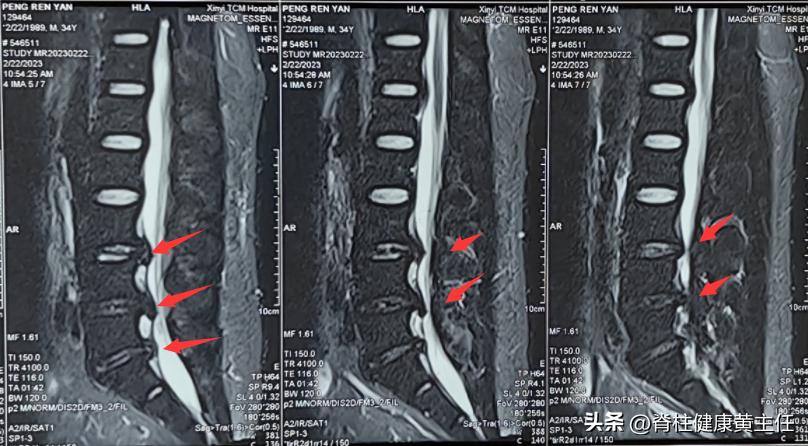

2023.2.22外院腰椎MR报告:L3/4、L4/5、L5/S1椎间盘膨出并突出,L3/4、L4/5水平椎管狭窄,L4/5、L5/S1双侧侧隐窝狭窄并神经根受压。

2023.03.18外院腰椎CT报告:L3/4、L4/5、L5/S1椎间盘向后突出,相应硬膜囊受压,L4/5、L5/S1双侧神经根受压。